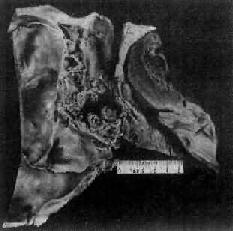

肉眼观:早期病例常表现为局部粘膜粗糙或稍隆起。有些原发癌可形成隆起于粘膜的小结节(图9-1),肿瘤逐渐发展可表现为结节型、菜花型、粘膜下型、浸润型或溃疡型(图9-2)肿块。据统计,结节型占41.4%,菜花型占17.5%,粘膜下型占15.1%,浸润型占12.7%,溃疡型占2%,分型不明者占11.3%。

图9-2 鼻咽癌